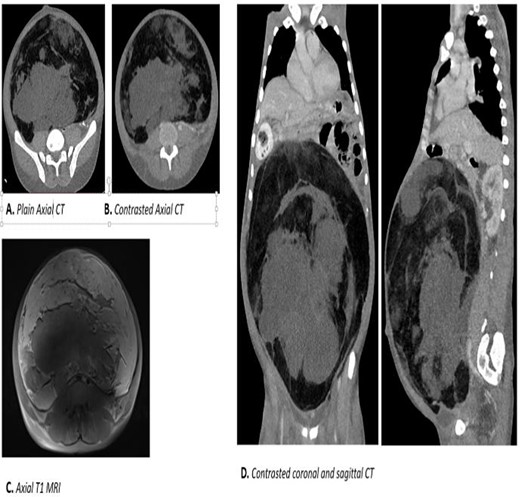

Laboratory results were normal except for microcytic hypochromic anemia with hypoalbuminemia of 2.4 mg/L (Fig. 2):

Abdominal and pelvic MRI: showed a huge mass from the pelvis extending to the abdomen measuring approximately 17 × 26 cm2.

Abdominal-pelvic CT-Scan: a large solid mass measuring 35.91 × 31.83 cm2 displacing the viscera and causing bilateral hydronephrosis.